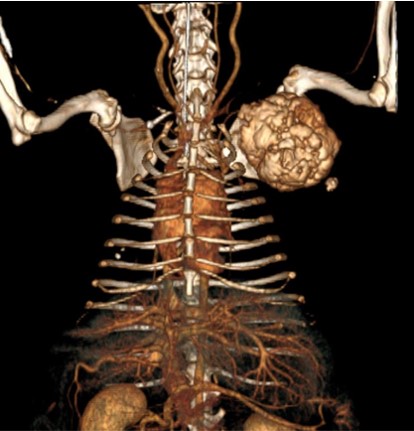

CT는 신체의 여러 각도에서 x-선을 투과시킨 후 단면 영상과 3차원적 입체영상을 얻을 수 있어 해부학적 구조와 병적 변화 정도를 정확하고 빠르게 평가할 수 있습니다.

CT 검사는 각종 종양과 염증, 외상 및 신체 기형과 같은 질환의 진단에 유용하게 사용될 수 있으며 수술이 지시되는 경우에도 진단을 넘어 정확한 해부학적 구조의 평가가 가능해져 이를 통해 수술 계획을 수립할 수 있습니다.

건국대학교 동물암센터에서 보유하고 있는 CT는 여러 개의 디텍터를 갖고 있는 multi-detector CT (MDCT)로써 촬영 시간 및 피폭량을 최소화 할 수 있는 장점이 있습니다. 여러 개의 디텍터를 통해 선명한 영상을 빠르게 구현해 냄으로써 진단의 정확성을 높일 수 있습니다.

- 종양 진단 (두경부, 흉강, 복강, 사지 골격) 및 전이 평가

간 종양 -

비장종양 -

견갑골 종양 -